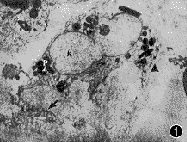

1.足突细胞特征:16例标本中,9例患者的视网膜表面膜组织中可见一种细胞边缘伸出大量足突(lamellipodia)的细胞,这些足突长短不一,或卷曲或伸直,并和细胞外纤维状胶原接触(图1~3)。足突细胞的外形主要呈现两种类型:(1)肾形或不规则形,胞浆内常有丰富的色素颗粒;(2)为长肾形(梭形),基本不含色素颗粒。这两种类型的细胞胞浆内细胞器异常丰富,在梭形性细胞中微丝更明显。在有色素颗粒的细胞周围,可见纤维性胶原分布,但是在每个细胞周围的分布程度有差别,无色素颗粒细胞周围胶原分布无规律,可以很丰富,也可能缺乏。

图1~3 带有色素颗粒的肾形足突细胞,可见一长足突(箭头示)和短足突(▲),P示色素颗粒,N示细胞核 ×9000